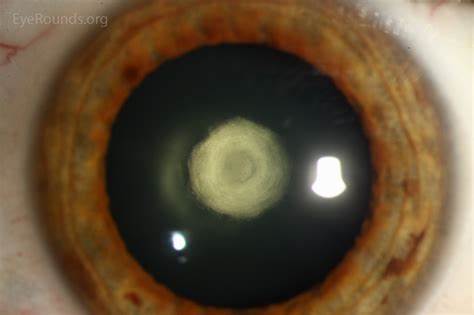

CATARACT SERVICES

• MICS PHACO EMULSIFICATION

• PREMIUM INTRAOCULAR IOL IMPLANTATION

• MULTIFOCAL, ADVANCE MONOFOCAL, TRIFOCAL IOL IMPLANTATION

• SCLERAL FIXATED IOL IMPLANTATION

• ANIRIDIA IOL IMPLANTATION

• CATARACT SURGERY IN HIGH RISK CASES LIKE POSTERIOR POLAR, HYPERMATURE CATARACT, WEAKER ZONULES, NON-DILATING PUPIL, POST UVEITIS CATARACT, POST RETINA SURGERY CATARACT, CATARACT WITH CORNEAL OPACITY UNDER TOPICAL ANAESTHESIA

CATARACT SERVICES Gallery